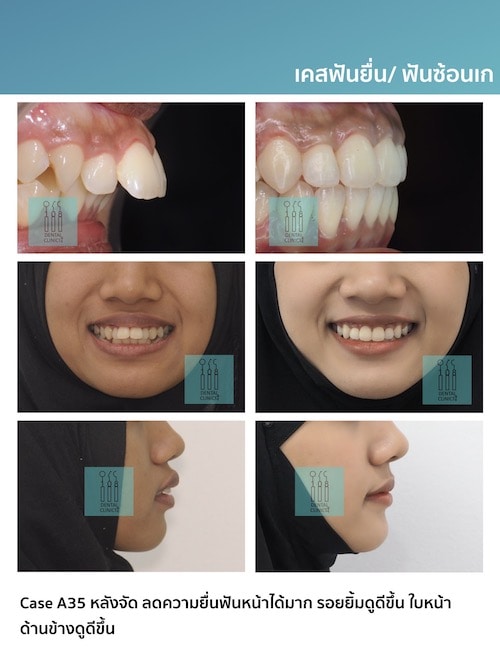

รีวิวเคสจัดฟัน

Review

ติดตามตัวอย่างผลงานเคสจัดฟันของทางคลินิกทันตกรรม 108 ได้ที่

เพื่อให้ทุกๆท่านมั่นใจในคุณภาพการรักษาของทางคลินิก เรายังมีเคสรีวิวอีกมากมายให้คนไข้ได้รับชมและพิจารณานะคะ มาขอดูเคสตัวอย่างแบบชัดๆ 4k retina ไร้ลายน้ำ กันได้ที่เคาน์เตอร์บริการของคลินิกทันตกรรม 108